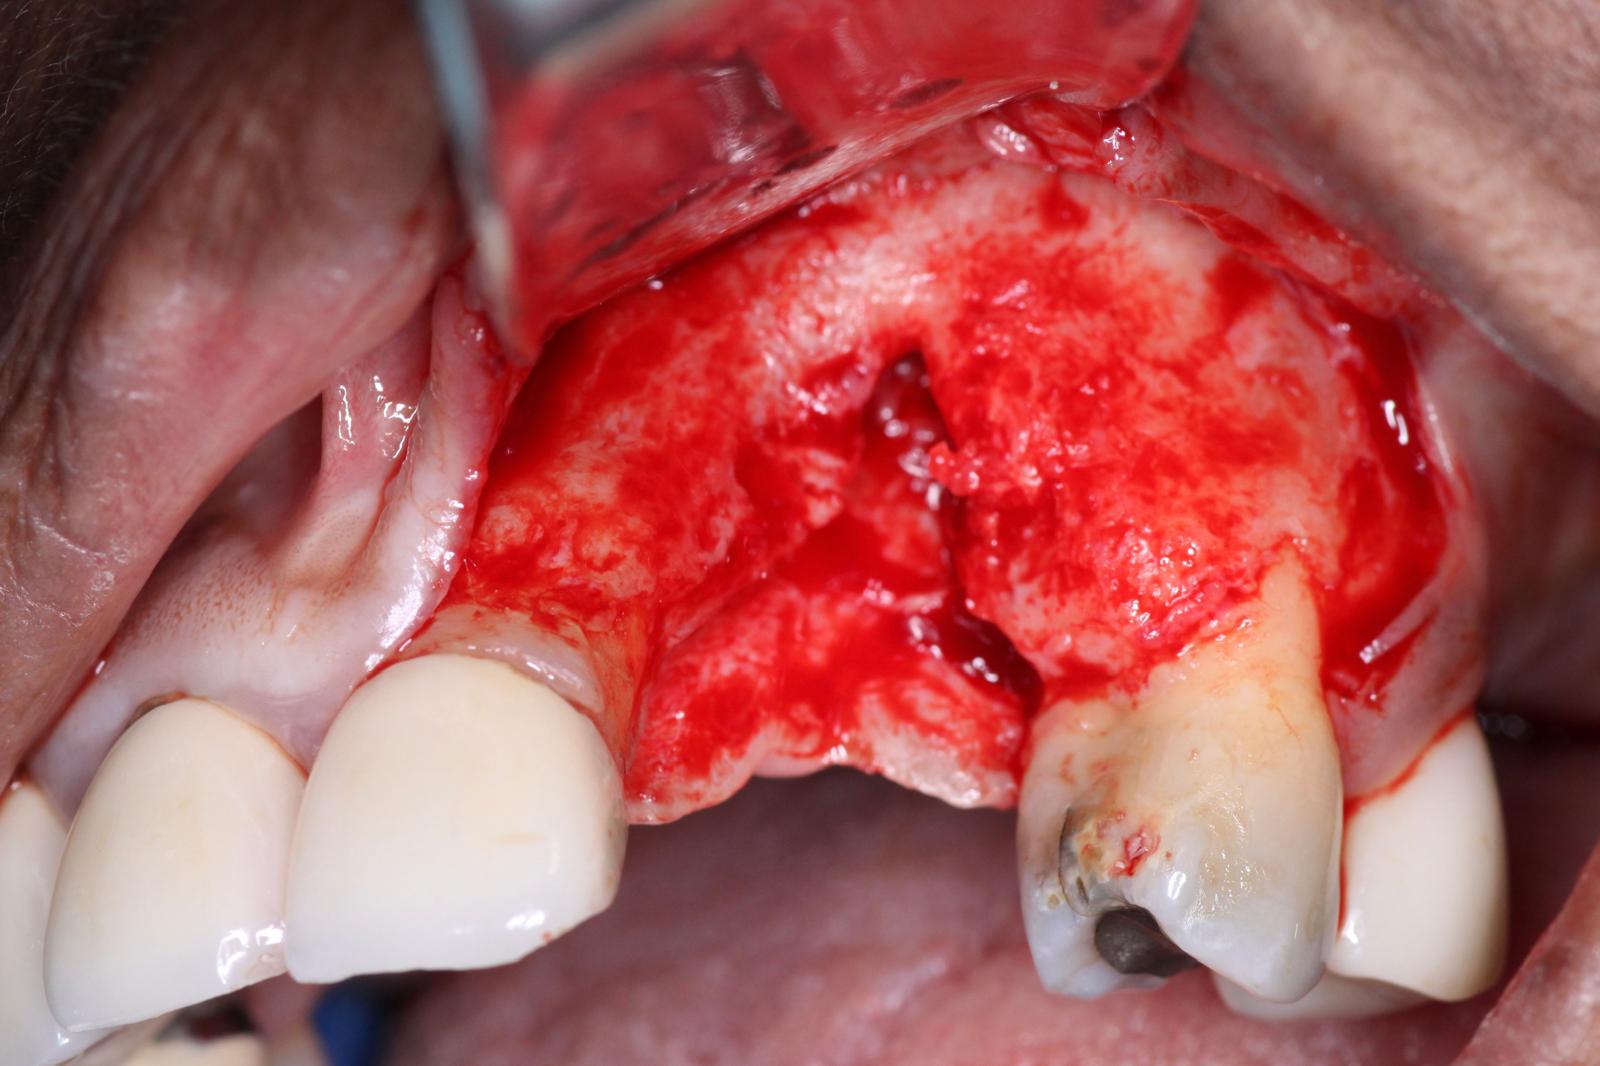

In the second part of our grafting technique, a DALI Amnion Chorion Membrane was layered over the bone graft, before we covered the entire site with a collagen membrane. The rationale for using an Amnion membrane here is that given the difficult nature of this GBR, we wanted to take advantage of the unique biological benefits of Amnion membranes, such as their inherent growth factors and anti-bacterial properties, to maximize the healing of the site and and enhance regeneration. For additional information on using Amnion membranes for this purpose, please see Enhance GBR and Improve Implant Surgical Outcomes with Amnion-Chorion Membranes

Next, we folded over the OsseoSeal collagen membrane to cover the bone and extend onto the native bone margins. It is crucial to try to cover everything and create a large enough space for the graft material to heal.